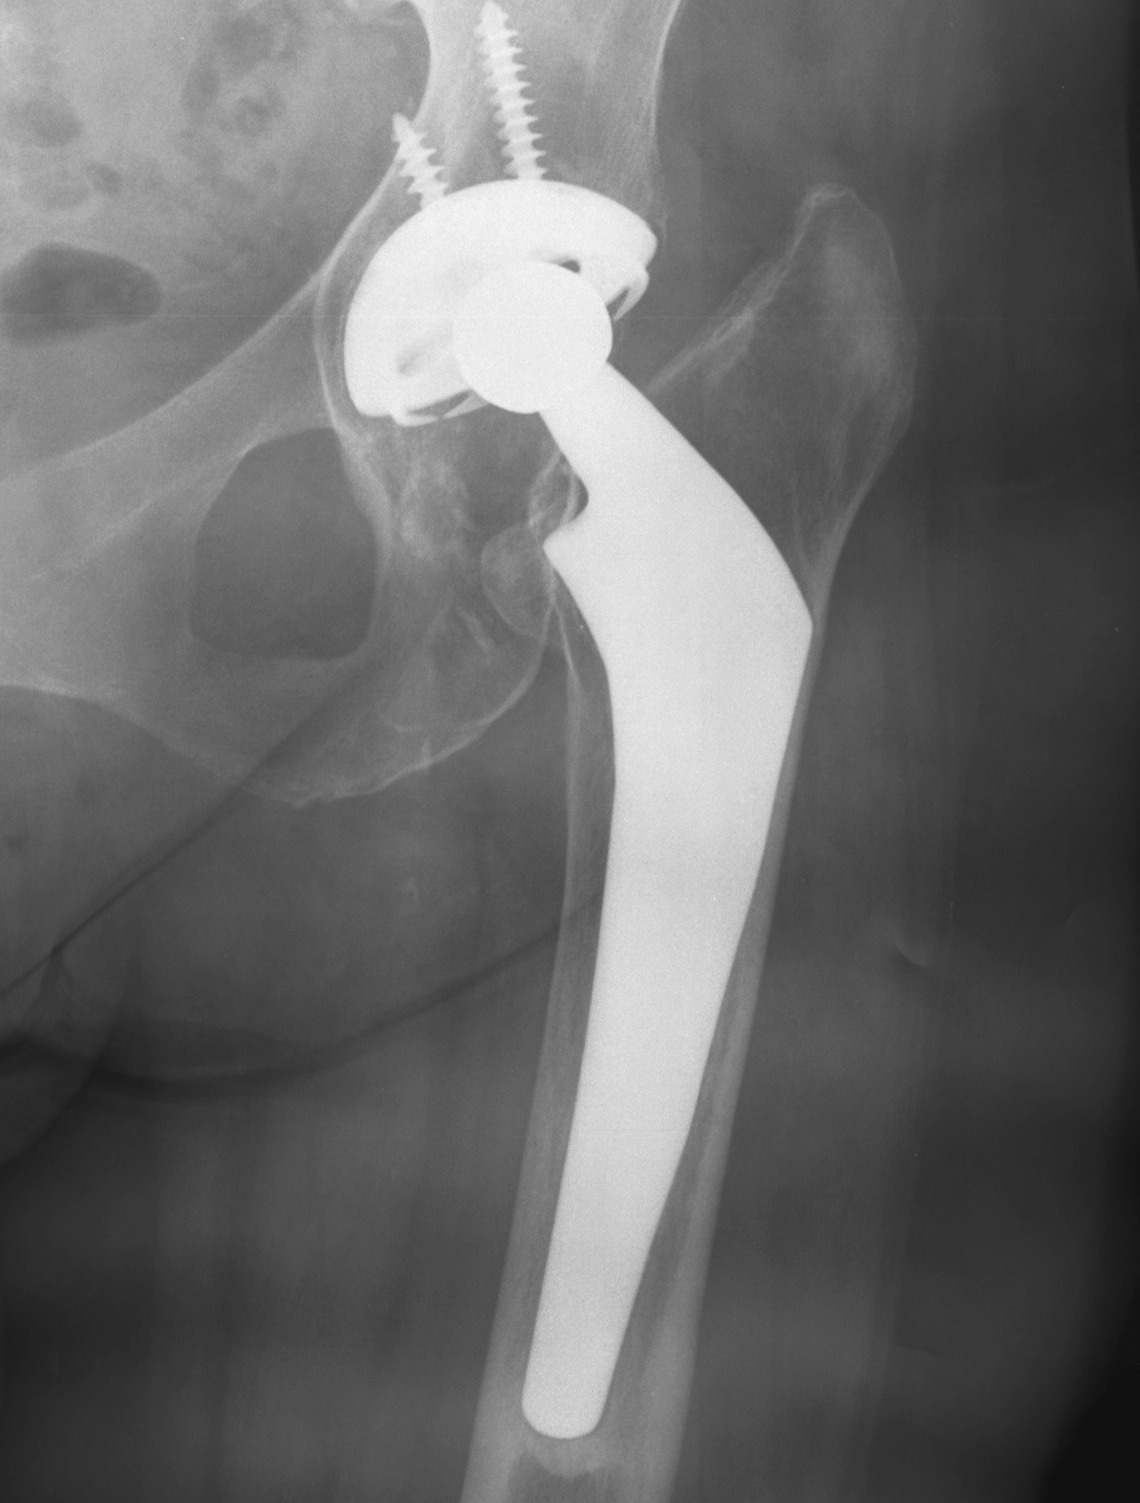

Cemented Femur

Signs of cemented femoral component loosening

O'Neil & Harris JBJS Am'84

1.  Possible

Bone-cement lucency < 50% total

- may be due to poor cementing technique

- loosening if progressive

2.  Probable

Cement-implant radiolucent line >2mm wide

- progressive

3.  Definite

1.  Cement fracture

2.  Femoral stem fracture

3.  New lucency cement - implant interface

4.  Stem migration

THR Probably LooseTHR Exeter Stem Fracture

A.  Subsidence

- 1-2 mm normal in first year

- > 5 mm abnormal

- measure from tip GT to head neck junction

B.  Medial midstem pivot

- pivots about midstem

- proximal medial, distal lateral

- poor cement superomedial or inferolateral

C.  Calcar pivot / bending cantilever

- distal fix strong, but proximally loose

- breakdown of proximal cement

- bone destruction